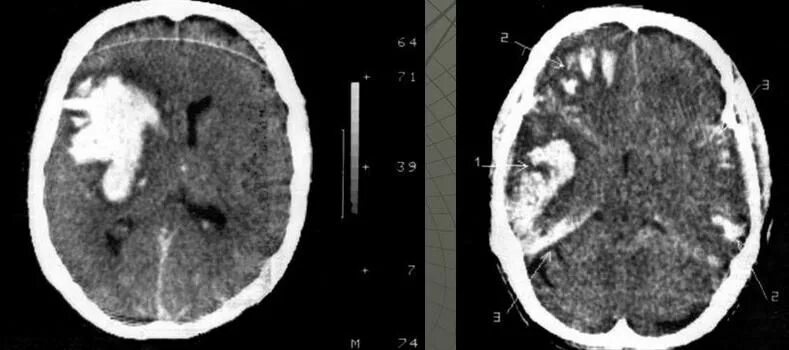

Ушиб мозга на кт